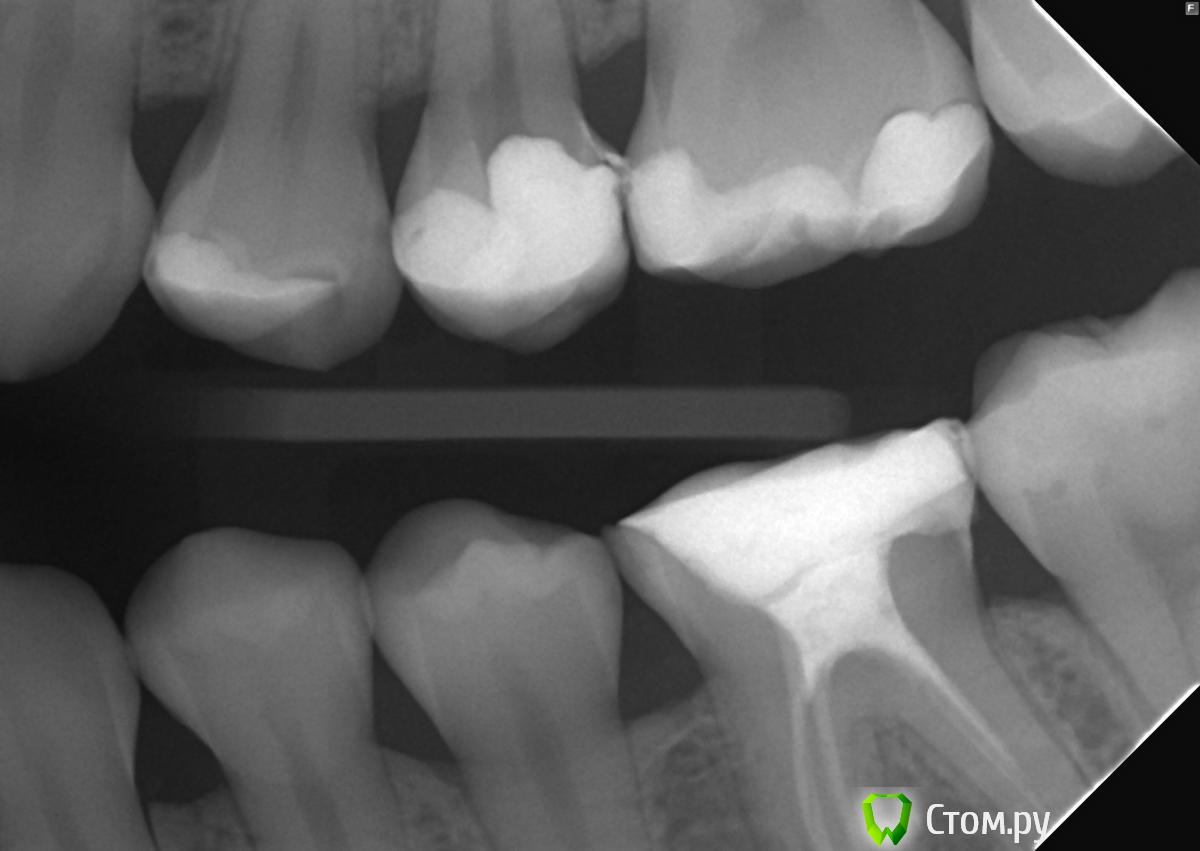

felicidade Опубликовано 25 сентября, 2014 Поделиться Опубликовано 25 сентября, 2014 Добрый день! Хотелось бы спросить мнение докторов относительно зубов 24 и 26: 1) судя по рентген-снимкам, у меня в 24 зубе кариес под пломбой. Скажите, пожалуйста, насколько он кажется близким к нерву? Может, я зря записалась к обычному терапевту, и мне надо сразу топать к эндодонту?2) зуб 26: виден ли там вторичный кариес? Я меняла пломбу в апреле этого года и заплатила то ли 5, то ли 6 тысяч за этот зуб, под прежней пломбой уже был кариес. Было бы очень обидно узнать, что новую пломбу надо снова менять Спасибо заранее и хорошего дня Ссылка на комментарий

felicidade Опубликовано 25 сентября, 2014 Автор Поделиться Опубликовано 25 сентября, 2014 Спасибо, доктор!Зуб 26 внешне выглядит безупречно, поэтому спросила на всякий пожарный, а вот вдоль пломбы у 24 зуба появилась коричневая кайма+под всеми остальными пломбами, который ставил этот доктор, в течение года образовался кариес, и их пришлось менять этой весной. Поэтому приготовилась к худшему Ссылка на комментарий

Korel Опубликовано 25 сентября, 2014 Поделиться Опубликовано 25 сентября, 2014 появилась коричневая кайма Может и пломбы менять нет необходимости, ограничившись только полировкой. Всё решит очный осмотр. Ссылка на комментарий